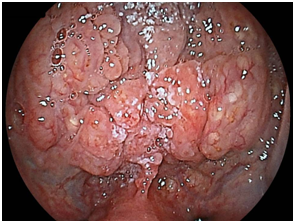

We detected 11 cases of superficial squamous cell carcinoma of the base of the tongue between April 2012 and March 2016. All the patients were complicated with current (n=3) or previous (n=8) esophageal squamous cell carcinoma. The patient characteristics are shown in Table 1. The mean age of the patients was 63.7years (range, 49-73years), and all patients were male. Four cases were diagnosed using trans-nasal endoscopy with the FICE system, seven cases were diagnosed using trans-nasal endoscopy with the LASERIO system. The average time to complete a thorough examination for one patient was approximately from 1 to 2minutes, regardless of the presence of abnormal findings. Biopsy specimen were obtained in all patients, and diagnosed as squamous cell carcinoma pathologically. Table 2 shows the treatment results. Five lesions were flat type (Figure 4A), four were elevated (Figure 4B), and two were depressed (Figure 4C). Regarding the tumor size, eight were T1, three were T2. No lymph node metastasis was detected in any case. Six cases were treated by endoscopic laryngo-pharygeal surgery,15 and 3 cases were treated by chemo-radiotherapy. One case was followed because of esophageal cancer. One case was treated by trans-oral robotic surgery at another hospital. For the seven resected specimens, the median tumor thickness was 800μm (range, 250-3000μm), and the median tumor diameter was 11mm (range, 10-25mm). Histologically, two of these lesions were squamous cell carcinoma in situ, five showed microinvasion of the subepithelial tissue. During a median follow-up period of 26months (range,11-56months), 1 patient, which patient’s tumor thickness was 3000μm, developed lymph node metastasis, which was treated by neck lymphadenectomy and chemo-radiotherapy. Three of the 11 patients cases were died of another disease, and 8 were alive as drafting this manuscript.

Figure 4B Elevated type.